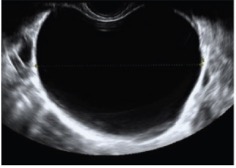

Guida al Counselling di Dicembre 2025: cistoadenoma dell’ovaio

vi presentiamo la guida al counseling di Dicembre 2025 sul Cistoadenoma dell’ovaio